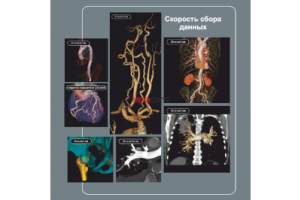

Система Optima CT660 предлагает новейшие достижения компьютерной томографии, удобство использования и широкие возможности применения в таких областях, как кардиология, онкология, сосудистая визуализация, а также динамическая визуализация.

- Новые возможности с детектором V-RES шириной 40 мм при скорости оборота 0,35 сек.

Скорость и охват (алгоритм IQE)

Разработанные компанией GE технологии спиральной реконструкции и поперечной коррекции пучка применяются одновременно, обеспечивая быстрое сканирование участка длиной до 70 см за 6 секунд с изотропным пространственным разрешением 0,35 мм.